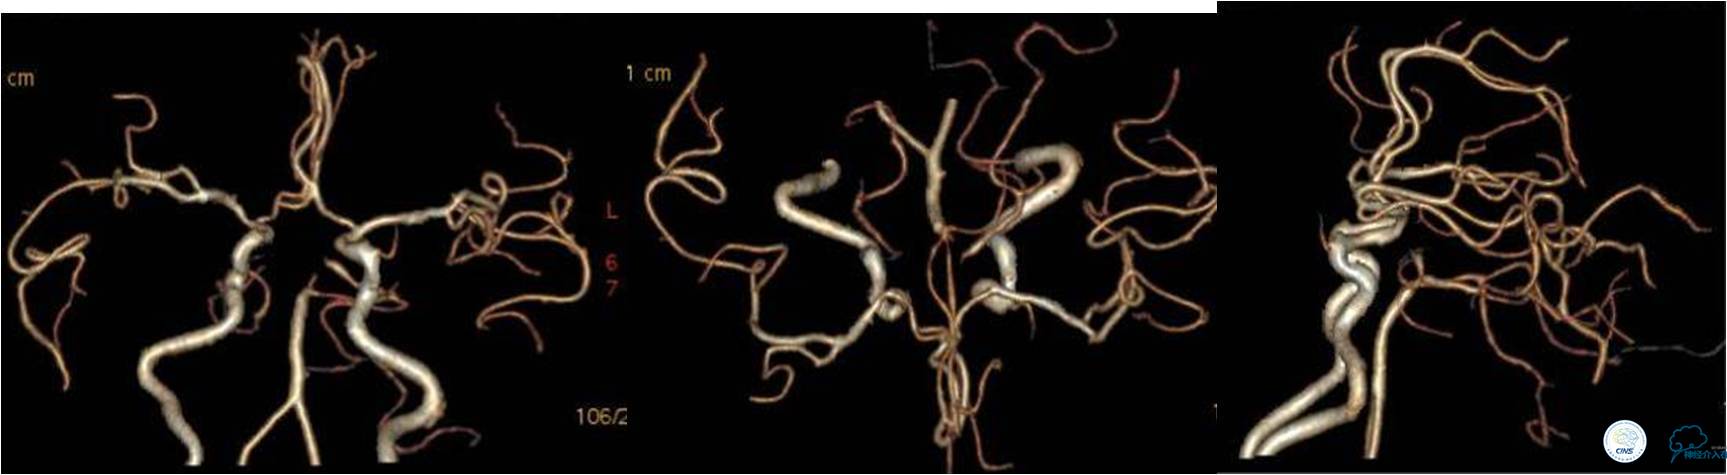

入院时颅脑CTA(发病4小时)

》DSA资料(左侧颈动脉)

》DSA资料(右侧颈动脉)

》DSA资料(左侧椎动脉)

》DSA资料(右侧椎动脉)